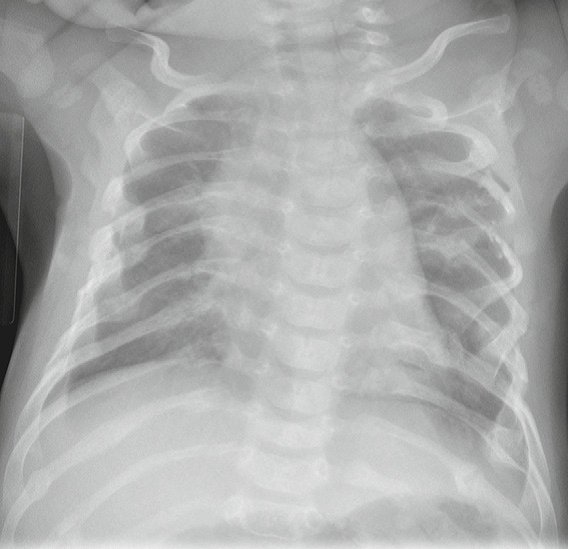

Fractures specific for NAT

• posterior rib fractures

• secondary to an adult squeezing an infant’s thorax

• close to costovertebral joints

• may be sutble prior to callus formation

• metaphyseal corner fracture

• extends through primary spongiosa of the metaphysis - the weakest portion

• secondary to forceful pulling of an extremity

• broken metaphyseal rim appears as a corner fracture triangular piece of bone when seen tangentially; or as a bucket-handle fracture when seen obliquely

• scapula

• spinous process

• sternum

• spiral long bone fractures in a nonambulatory child

• multiple fractures of varying ages